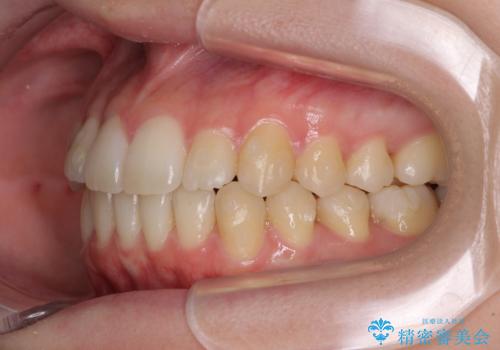

気になる前歯を整えたい インビザライン・ライトでの矯正治療

- ちょっとしたデコボコを整えたいとのことで来院された患者様です。

歯列不正は軽微であったため、インビザライン・ライトにより、費用を抑えて矯正治療を行うこととしました。

上下前歯の捻れが改善され、患者様には大変満足していただきました。